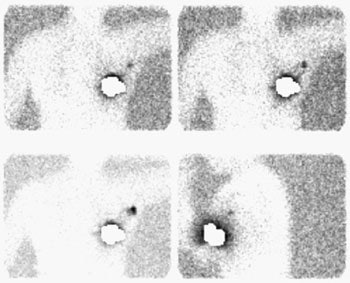

Sentinel lymph node imaging: The lymphoscintigraphy exam below was performed using a peri-tumoral tracer injection. Images were performed at 5, 10, and 15 minutes after injection in a LAO projection with the left arm behind the patient's head. A lead shield was placed over the breast. The exam demonstrated rapid localization of the primary lymphatic drainage to the axilla. Following the procedure the patient went to the operating room for gamma probe localization of the sentinel node. |

|